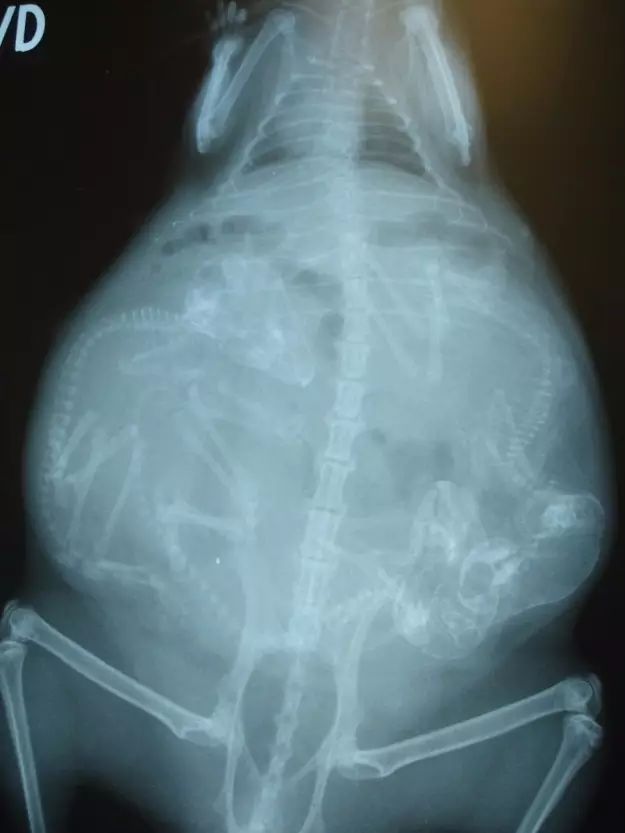

8. 天竺鼠。